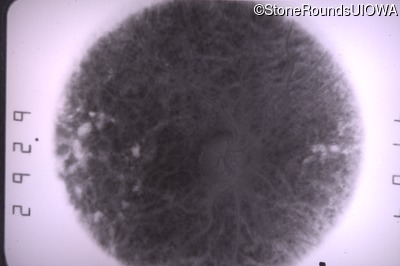

Goldmann Visual Field - Left - 20/20 sc

Exemplar